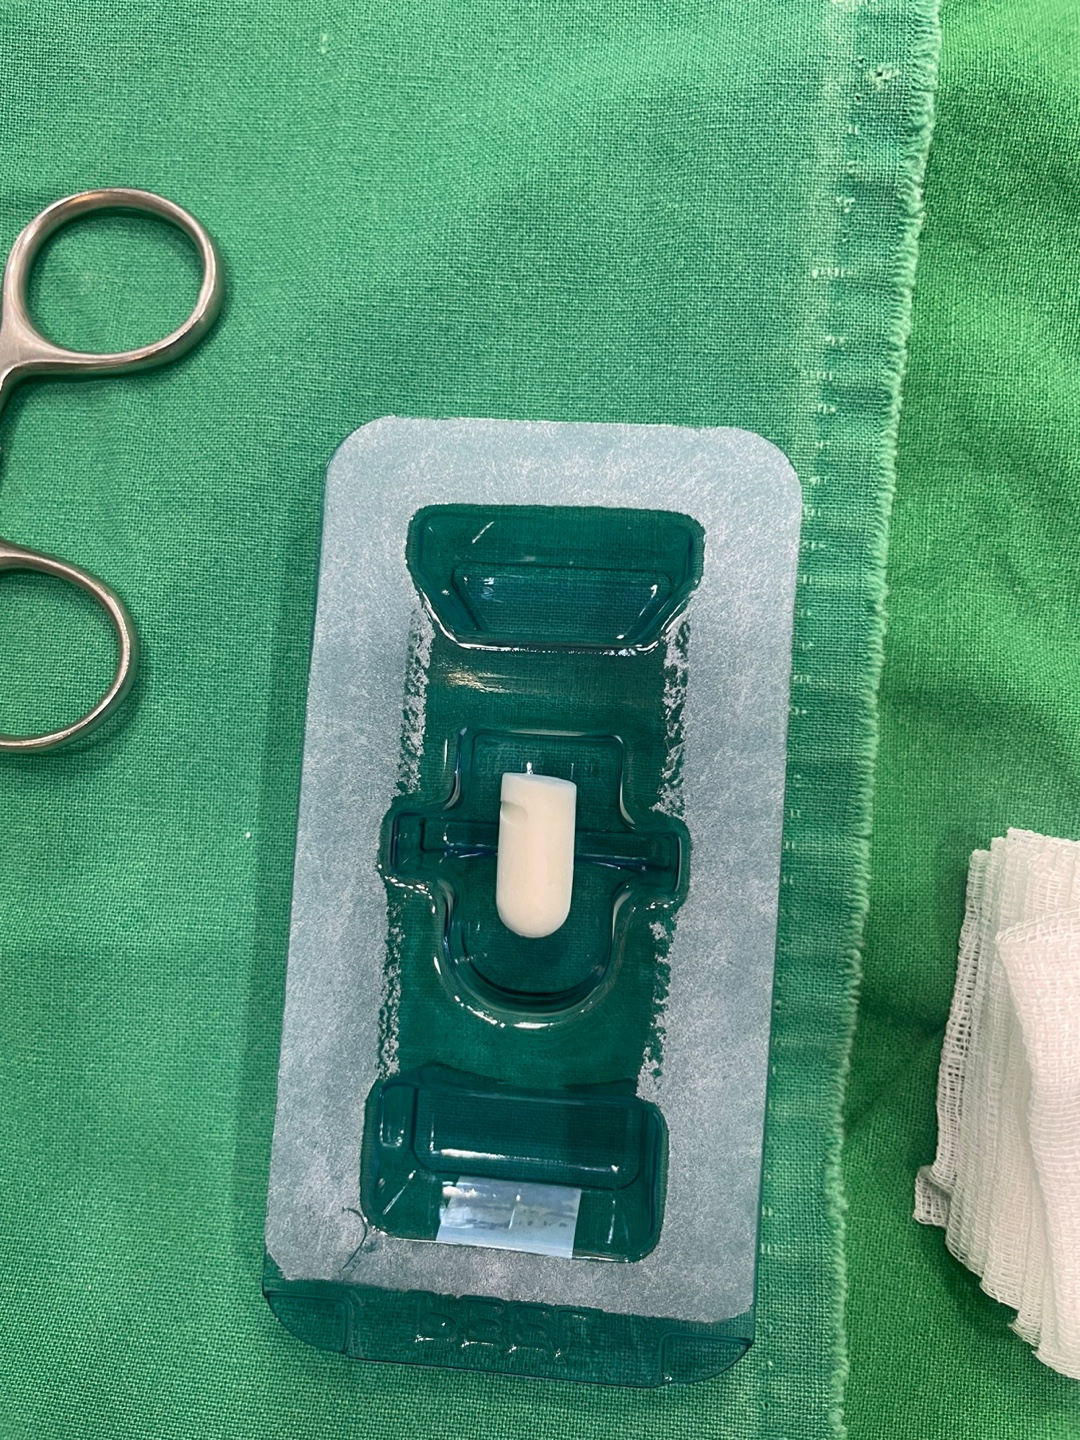

환자분께 사진 상세히 설명드리고 상담 2틀후인 오늘 수면 마취하에 사랑니 발치해 드렸습니다.